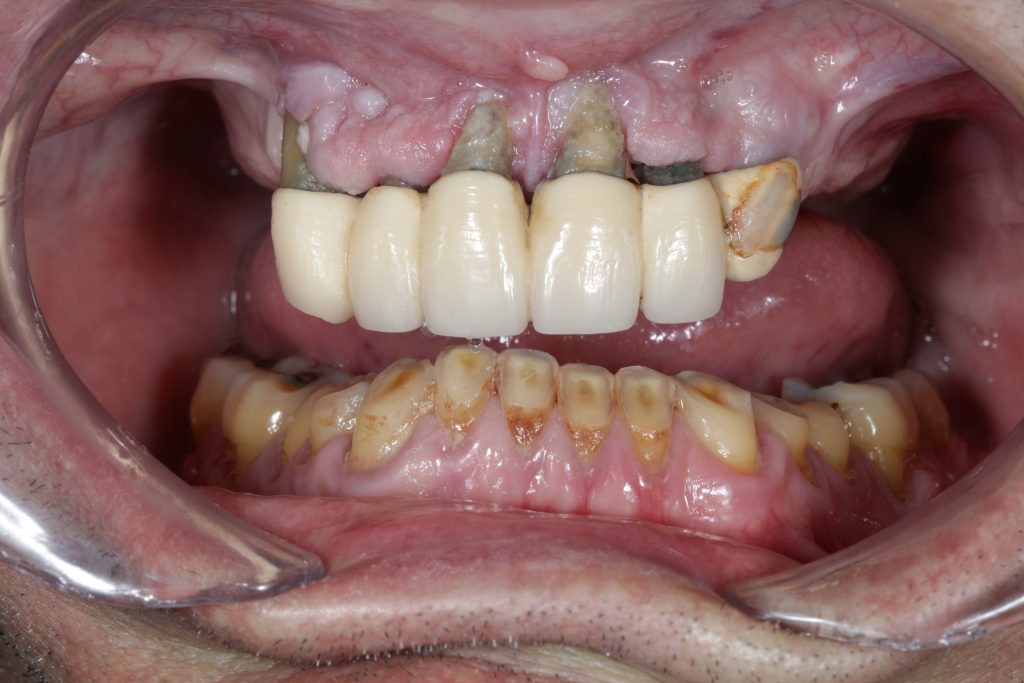

The use of CDP (Complete Digital Patient) as a basis for planning in a case of complete implant rehabilitation with a full arch in zirconia – ceramicised

Complete Digital Patient (CDP): guided surgery for complete upper and lower rehabilitation with zirconia-ceramic screw-retained implants

Complete Digital Patient (CDP): the use of guided surgery for implant restoration in total upper and lower rehabilitation with titanium bars and different types of zirconia-ceramic

Upper and lower prosthetic rehabilitation with titanium bars and translucent zirconia-ceramic structures. The CDP as an aid in communication between the entire team and the patient, who is the focus of the work.